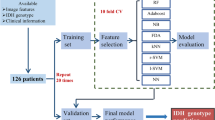

Machine learning methods have been introduced as a computer aided diagnostic tool, with applications to glioma characterisation on MRI. Such an algorithmic approach may provide a useful adjunct for a rapid and accurate diagnosis of a glioma. The aim of this study is to devise a machine learning algorithm that may be used by radiologists in routine practice to aid diagnosis of both: WHO grade and IDH mutation status in de novo gliomas.

To evaluate the status quo, we interrogated the accuracy of neuroradiology reports in relation to WHO grade: grade II 96.49% (95% confidence intervals [CI] 0.88, 0.99); III 36.51% (95% CI 0.24, 0.50); IV 72.9% (95% CI 0.67, 0.78). We derived five MRI parameters from the same diagnostic brain scans, in under two minutes per case, and then supplied these data to a random forest algorithm.

Machine learning resulted in a high level of accuracy in prediction of tumour grade: grade II/III; area under the receiver operating characteristic curve (AUC) = 98%, sensitivity = 0.82, specificity = 0.94; grade II/IV; AUC = 100%, sensitivity = 1.0, specificity = 1.0; grade III/IV; AUC = 97%, sensitivity = 0.83, specificity = 0.97. Furthermore, machine learning also facilitated the discrimination of IDH status: AUC of 88%, sensitivity = 0.81, specificity = 0.77.

These data demonstrate the ability of machine learning to accurately classify diffuse gliomas by both WHO grade and IDH status from routine MRI alone—without significant image processing, which may facilitate usage as a diagnostic adjunct in clinical practice.